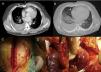

A 36-year-old-male, previously healthy, was admitted to the emergency department presenting a right parasternal knife stab wound in the third intercostal space after a street fight. On physical examination, no other lesions was detected except for ecchymotic lesions around the face and both arms. The patient remained hemodynamically stable. Despite the location and depth of the stab wound, the patient presented no clinical signs of cardiac trauma (no jugular distention, hypotension or tachycardia), normal ECG and no increase in cardiac enzymes. The initial chest radiography showed no abnormalities and transthoracic echocardiography showed no pericardial effusion. Because of the patient's hemodynamic stability and uneventful initial course, conservative management was adopted. However, three hours after admission signs of progressive anemia and low hematocrit in laboratory tests were observed (hematocrit 24%; hemoglobin 8 g/dl), suggesting internal bleeding. Echocardiography was accordingly repeated, which remained normal. A chest computed tomography (CT) scan was then performed to investigate internal bleeding, which showed the trajectory of the chest stab wound and severe right-sided hemothorax. No pericardial tamponade was detected by echocardiography (Figure 1A and B). The patient was immediately taken to the operating room for surgical review, via a median sternotomy because of the stab wound trajectory. A 1-cm parasternal incised wound was located crossing the chest (Figure 1C). No pericardial effusion or cardiac tamponade was seen. However, a concealed active bleeding atriopleural fistula connecting the right atrium (RA) and draining into the right pleural cavity was detected (Figure 1D). The wound path crossed the mediastinum and pleura and reached the RA manifesting as an atriopleural fistula. Massive right-sided hemothorax was confirmed. The wound in the RA had presumably been draining into the right pleural cavity from the time of the street fight until surgery, due to the negative pressure generated by respiratory movements. The size of the pleural cavity enabled a large quantity of blood to accumulate without hemodynamic instability. This mechanism caused a massive pleural effusion and prevented initial cardiac tamponade, and was the reason that the patient remained hemodynamically stable during the first hours after the fight. The injury to the RA was repaired by direct suture with a non-absorbable 4-0 polypropylene suture buttressed with Teflon felt, and the right pleural effusion was drained (Figure 1E). A chest drain was placed and removed two days after surgery. The patient was discharged uneventfully five days after surgery.

Computed tomography images showing (A) chest stab wound (arrow) and severe secondary right hemothorax with different densities inside suggesting different stages of bleeding (*) and (B) no pericardial effusion; (C) median sternotomy showing parasternal stab wound with no active bleeding (arrow); (D) active bleeding stab wound in the right atrium (arrow); the right lung is covered by the pleura (*); **: pericardial membrane; (E) stab wound in the right atrium sutured with a polypropylene suture buttressed with Teflon felt (arrow). The right lung is visible as the pericardium and right pleura are open (**). RA: right atrium; RL: right lung; RV: right ventricle.